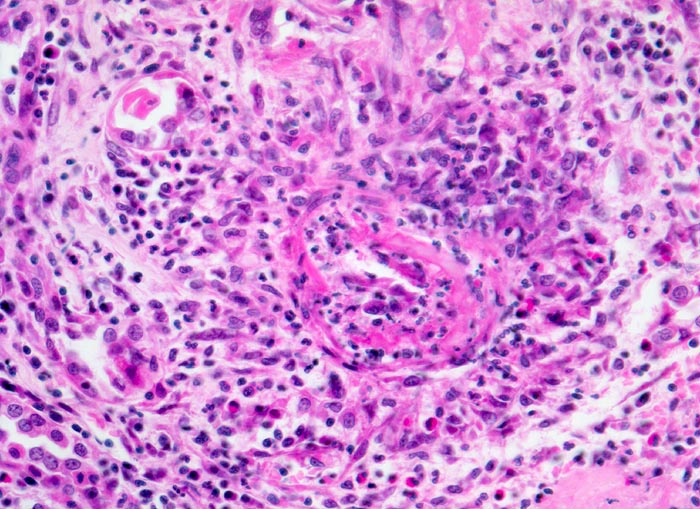

PathoPic – image database / PathoPic ID 4251 - Polyarteritis nodosa Makroform: akute Phase

Polyarteritis nodosa Makroform: akute Phase

Kleinere Arterie mit einer nicht ganz frischen zirkulären fibrinoiden Gefässwandnekrose. Die Gefässwand ist stellenweise vollständig unterbrochen. Das ganze Gefäss ist mantelförmig umgeben von einem gemischten Entzündungsinfiltrat aus neutrophilen und eosinophilen Granulozyten, Lymphozyten, Plasmazellen und zahlreichen Histiozyten mit länglichen Kernen. In der Gefässwand selbst sind zerfallende neutrophile Granulozyten erkennbar.

Makroskopischer Befund der Nieren: Vergrösserte Nieren mit Petechien und mehreren frischen, teils hämorrhagischen Infarkten.

Infolge transmuraler Nekrosen kommt es zur Ausbildung von Aneurysmata (Aneurysma spurium). Diese sind angiographisch nachweisbar.